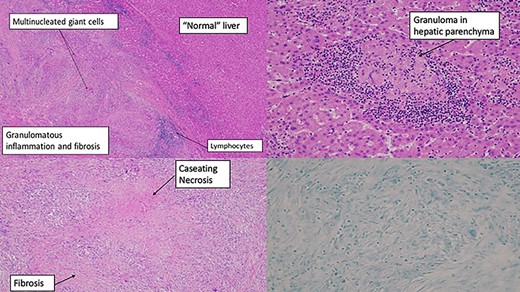

Based on these findings, the decision was made to proceed to open resection. An open left hemihepatectomy was performed with complete removal of the mass. Histopathology revealed necrotizing granulomatous inflammation (Fig. 3). Mycobacteriology assessment revealed no acid-fast bacilli. However, mycobacterial nucleic acid amplification testing

(A) resected liver specimen—routine formalin-fixed tissue stained with haematoxylin and eosin. Granulomas and fibrosis with demarcation with adjacent normalish liver parenchyma. (B) Resected liver specimen—routine formalin-fixed tissue stained with haematoxylin and eosin showing a necrotizing granuloma surrounded by lymphocytes within the liver parenchyma. (C) Biliary duct—routine formalin-fixed tissue stained with haematoxylin and eosin. Granulomas centred around an intrahepatic bile duct, replacing some of the epithelium. (D) Bottom right—Ziehl–Neelsen stain (negative for acid-fast bacilli)

(GeneXpert Assay {IS6110}) identified deoxyribonucleic acid for Mycobacterium tuberculosis, and mycobacterial culture of the operative specimen cultured the same, with a sensitivity profile suggestive of drug-susceptible tuberculosis. The patient had an uncomplicated post-operative course and is successfully undergoing medical management for hepatic tuberculosis.